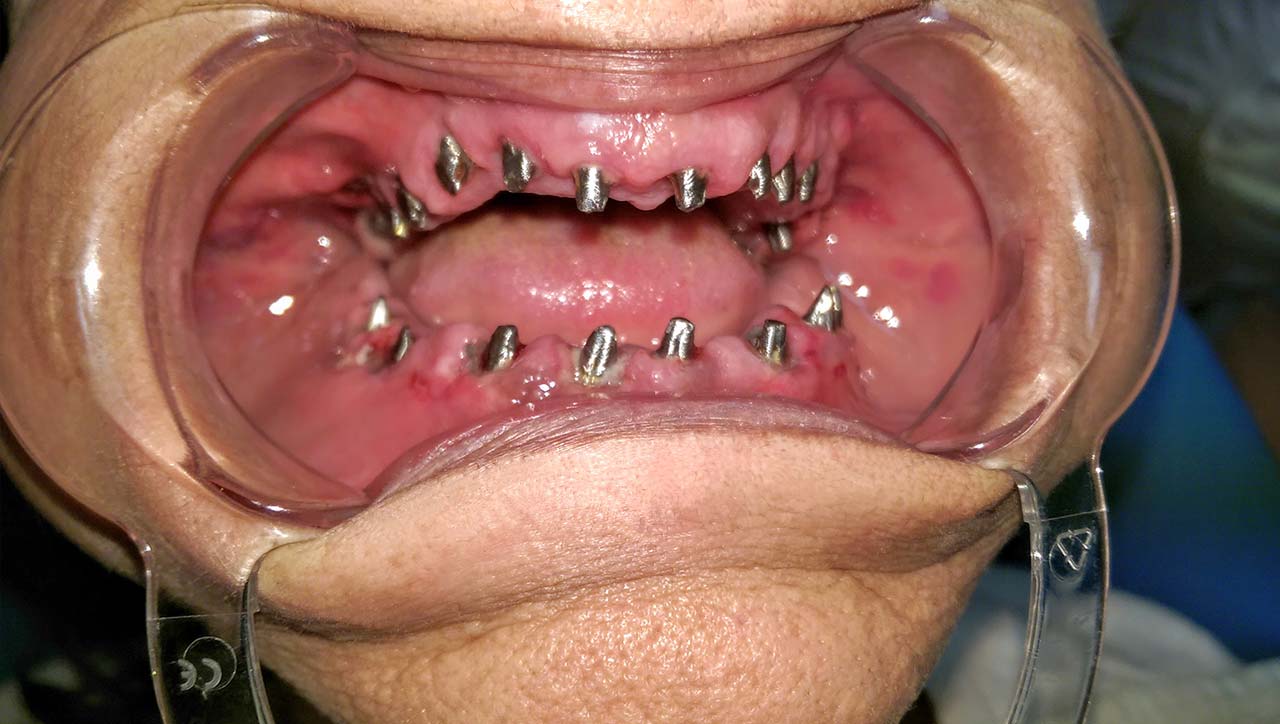

Elhanyagolt fogsor cseréje 2 nap alatt

2 nap alatt varázsoltuk ezt a szép esztétikus alsó, felső körhídat implantátumokkal megtámasztva a korábban elhanyagolt szájba. Az 1. nap 26 fogat távolítottunk el, mert annyira rossz állapotban voltak, és rögtön azonnal terhelhető IHDE svájci implantátumokat raktunk be, fentre 8, lentre 6 darabot. A sebeket összevarrtuk és intraorális szkennerrel digitális lenyomatot vettünk. 2 nap múlva pedig beragasztottuk a kész PMMA műanyag körhidakat. Dr. Kelemen Péter és a Symbion Fogtechnika munkája.